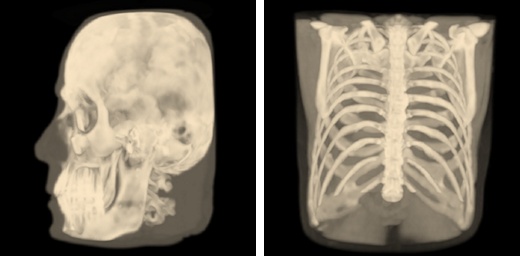

Isosurface Visualization¶

This method suits for bones, skin surface and segmented areas visualization. The base of this method is a search of intersection points between the rays corresponding to pixels and the isosurface. The user selects the level of the isosurface and the clipping plane position with sliders.

Max Intensity Projection (MIP)¶

The method suits for the primary analysis of the initial data, as it does not require setting values of any parameters. This method is based on computation of the maximum values for intensities of the original data along the rays passing through the pixels.